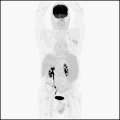

PET/CT — Pulmonary Tuberculoma

Combined PET/CT scan showing FDG-avid pulmonary tuberculoma in the chest

PET Downloaded 2026-03-15

Pet

Fdg

Wikimedia Commons: PET-CT of a tuberculoma.png